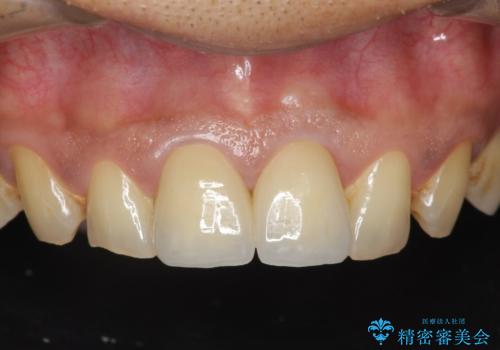

[ジルコニアクラウン治療] 笑った時に目立つ銀歯を白くしたい

![[ジルコニアクラウン治療] 笑った時に目立つ銀歯を白くしたいの症例 治療後](https://seimitsushinbi.jp/wp/wp-content/uploads/2020/07/b5a325afedd469212bae5e25910ae923-500x350.jpg?v=1595071338)